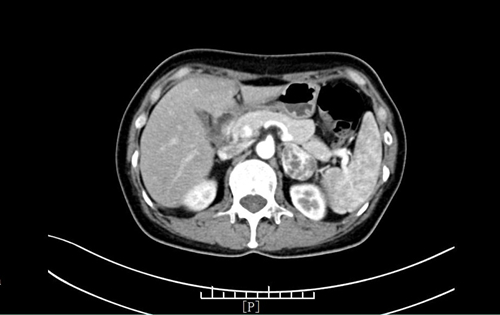

45岁的王女士(化名)常规体检行胸部CT检查,发现左肾上腺区占位。入院增强CT检查提示患者左侧肾上腺区占位性病变,动脉期明显强化。通过细致问诊和查体,泌尿外科何晓亮主任考虑其为嗜铬细胞瘤可能较大,并耐心地向患者及家属告之病情。考虑到该手术难度高,风险极大,术前准备时间长,泌尿外科组织开展了肾上腺肿瘤MDT,积极研讨病情,制定了完善的诊疗方案。经过充分术前准备,患者各方面指标均趋于平稳,何主任团队决定为其安排手术,摘除这颗困扰王女士的“定时炸弹”。

患者周女士(化名),因“左腰部酸胀不适4月”入院治疗。CT检查发现,患者左肾上腺占位性病变,进一步检查发现患者促肾上腺皮质激素(ACTH)被抑制,皮质醇节律消失。内分泌科会诊后行小剂量地塞米松试验检查后,初步考虑为库欣综合征。通过介入与血管外科团队肾上腺静脉采血(AVS)后,最终确诊患者为左肾上腺肿瘤导致的库欣综合征。经过充分术前准备,泌尿外科何晓亮团队成功为患者摘除了功能性肾上腺肿瘤。